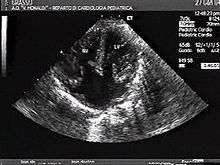

This is an echocardiography of "Complete" Atriventricular Canal Disorder. There is a clear absence of lower septum that would separate all four chambers of the heart

Atrioventricular canal defect may be divided into partial or complete forms. In the partial form, openings between the left and right atria and improper formation of the mitral valve exist. In the complete form, there is free movement in all chambers because there is a large hole where the atria and ventricles meet, and instead of there being two valves there is one common valve.[4]